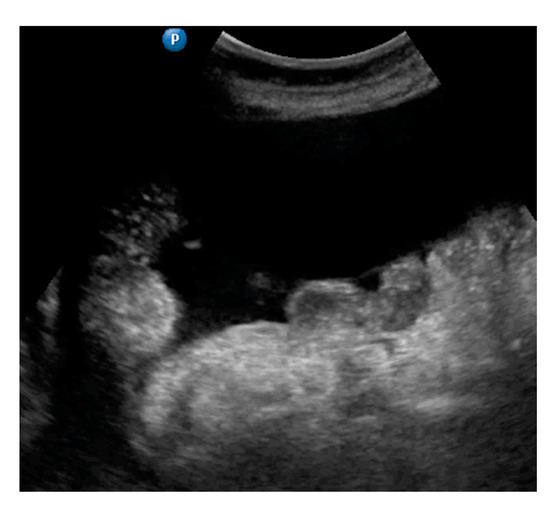

| Peritoneum, abdomen | Abdomen carcinomatosis manifest as hypoechogenic lesions over the peritoneal surface of the paracollic gutters or internal abdominal wall. | Figure 3 | Video S3 |